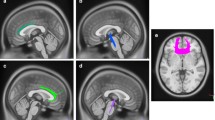

To localize cortical source activation of epileptogenic activity, a model of gray matter was constructed for each individual’s T1-weighted high-resolution volumetric MR image (see “Appendix”). We used a probabilistic brain atlas composed of 56 structures from manually delineated MRI data constructed by Shattuck et al. (2008) as a standard volumetric head model with each location specified in MNI305 coordinates. This atlas contains all cerebral lobes and, specifically, the right and left hippocampi, limbic gyri, insular cortices, caudate, putamen, cerebellum and brainstem. Excluding the cerebellum and brainstem reduced the number of anatomical regions to 27 in each cerebral hemisphere (Table 2; Fig. 1) (Shattuck et al. 2008). The realistic head model consisted of X-, Y- and Z- oriented dipoles at approximately 4000 locations such that every location represented the same amount of gray matter identified in the individual’s MR image. These MR images were coregistered with the individual’s digitized head shape recorded at the time of MEG data collection.

Left Cortical modeling of the brain in the MNI coordinates; the average cortical model and its surface in red. Right The delineated anatomical structures (Shattuck et al. 2008). Regions of this slice are color-coded according to their anatomical identification using MEG Tools. Note that the average cortical model is blurred and its surface is smooth as it is created from a large number of volumetric MRIs of normal individuals (40 cases) (Color figure online)